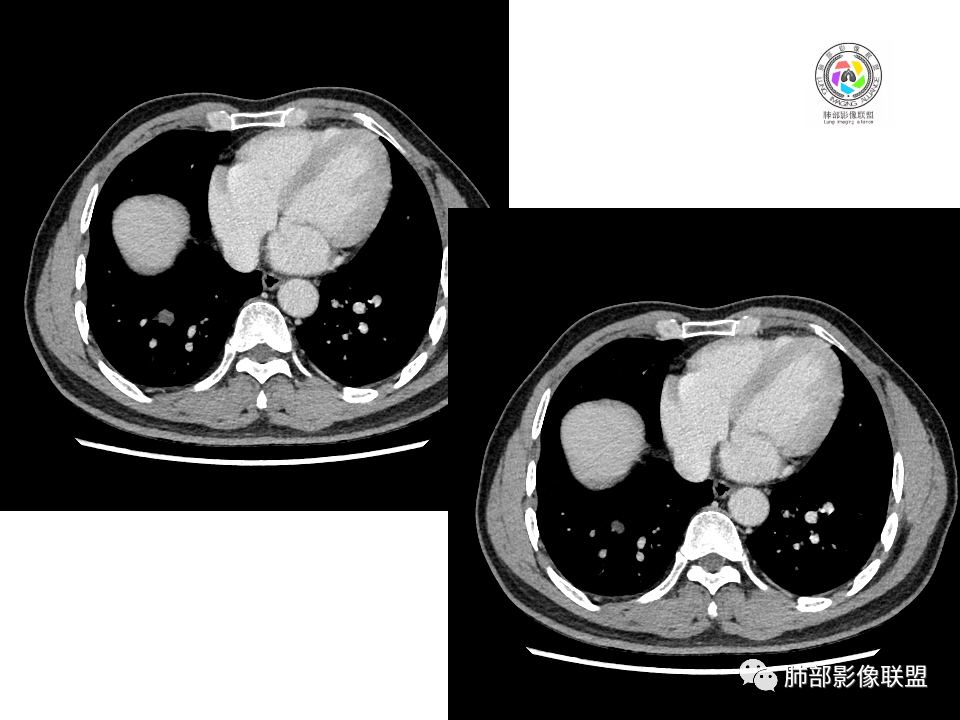

血管也是稍推移,在边缘,病灶密度均匀,边缘稍收缩;均匀强化;

这两个病灶的密度、强化、形态、边缘、与血管的关系类似;还是一元论吧。

右肺中叶病灶

GGO,与支气管关系密切

这个形态、与支气管关系,与前两个不一致,所以考虑独立炎性病变。